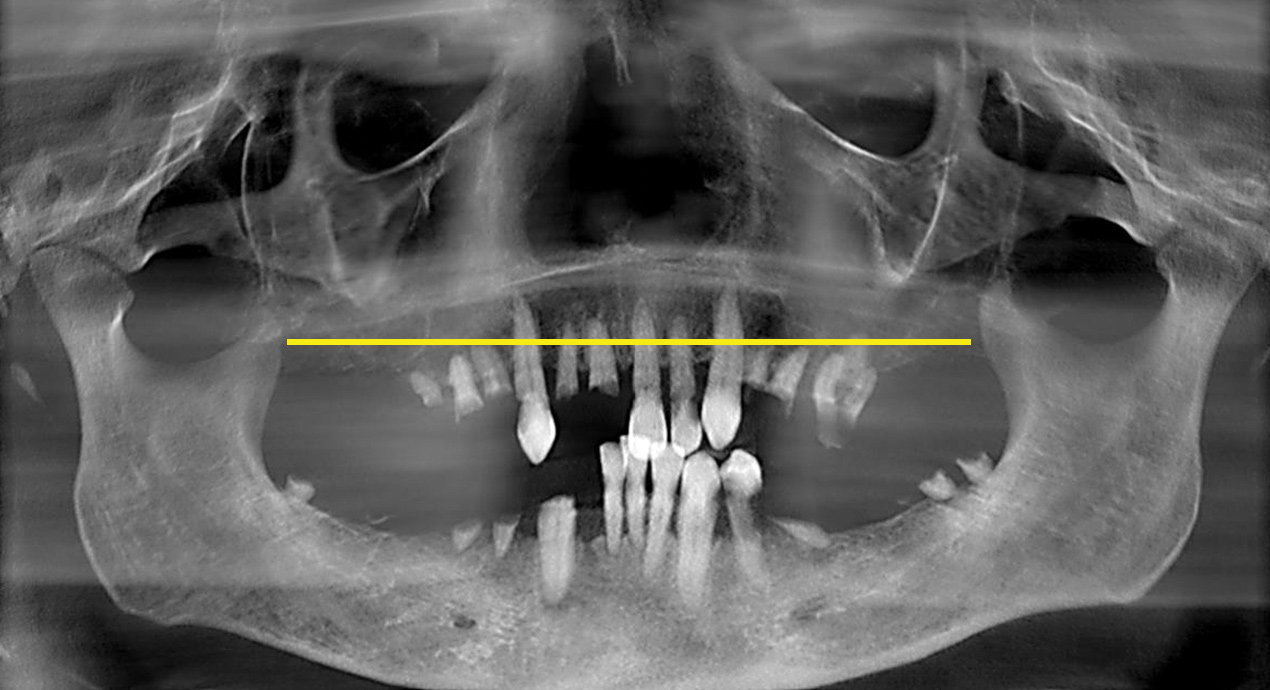

Fig 4. Presurgical panoramic radiograph of an All-on-4–style patient with pneumatized maxillary sinuses that extend beyond the planned horizontal plane of bone reduction (yellow line).

Figure 4

Pneumatized Maxillary Sinus Extending Below Bone Reduction Plane

It is well established that maxillary sinus pneumatization may occur following posterior maxillary tooth loss.24 In select cases, pneumatization of the maxillary sinus may extend beyond the anticipated horizontal plane of bone reduction required for All-on-4–style treatment (Figure 4). Failure to adequately reduce bone in these areas may lead to restorations of inadequate thickness that are at increased risk for fracture.25 Conversely, standard bone reduction in these areas may lead to significant damage to the Schneiderian membrane.

To overcome this complication, the author carefully reduces the residual maxillary crestal bone until crestal exposure of the Schneiderian membrane is achieved (Figure 5). On crestal visualization of the Schneiderian membrane, the author uses curettes to lift the membrane apically from the anticipated plane of bone reduction (Figure 6). The maxillary bone is then reduced apically, and the process is repeated until the desired amount of bone reduction is achieved. When performed in this manner, the Schneiderian membrane remains intact while crestal areas of reduced maxillary bone will have openings of varying degrees depending on the amount of bone reduction (Figure 7). The author does not augment these openings with bone graft and simply closes the surgical site with primary closures of thick mucogingival flaps. To date, patients receiving treatment from the author in this fashion have had no adverse outcomes (Figure 8).